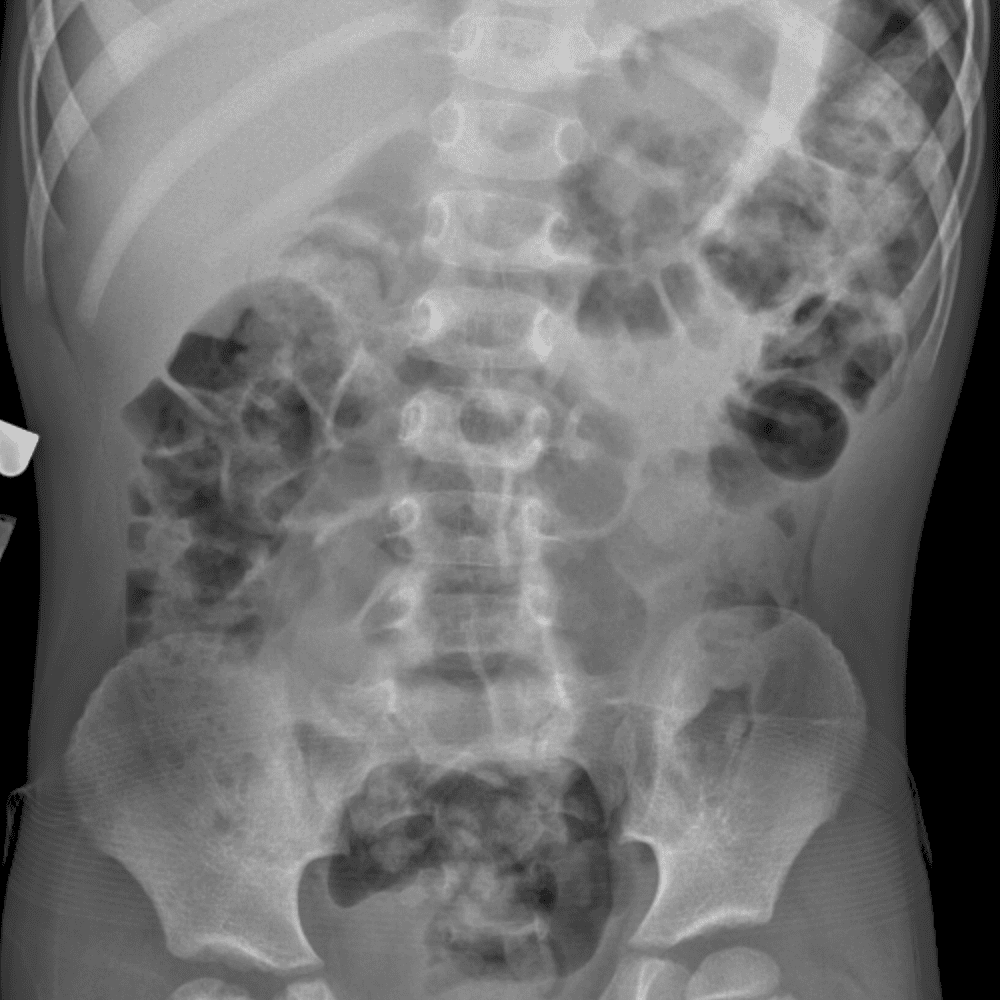

Peds Abdomen

Practice

Simulates call by including subtle or difficult cases and some normals.

30 cases